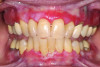

Erythematous/erosive/atrophic: Painful, red, raw mucosa, often on the gingiva (desquamative gingivitis), coexisting with reticulated areas (Figure 1).

Fig 1. Erosive lichen planus in a 47-year-old African American female patient. Erythematous, ulcerated lesions could be visualized at the gingival margin in both the maxilla and mandible. The patient reported significant discomfort associated with these lesions and aversions to acidic and hot foods due to pain after consumption.

Figure 1